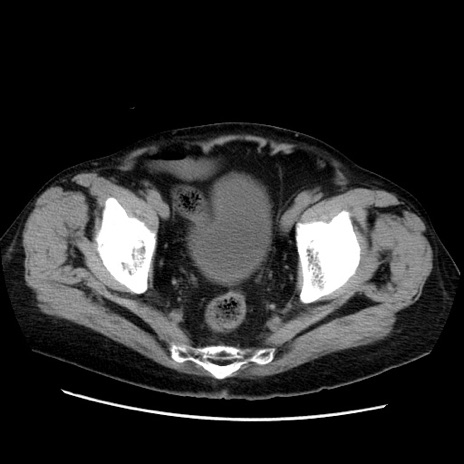

症例21(横断像)

【症例】70歳代男性

【主訴】腹痛

【現病歴】肝硬変・肝細胞癌にてかかりつけの方。約9時間前に食後より腹痛出現。症状が徐々に増悪し、嘔吐出現したため来院。

【既往歴】肝硬変、肝細胞癌(RFA、TACE後)

【身体所見】意識清明、表情苦悶様、BT 36℃、BP 129/78mmHg、P 88bpm、SpO2 97%(RA)、右上腹部から心窩部にかけて圧痛あり、反跳痛なし、筋性防御あり。

【データ】WBC 5800、CRP 0.16